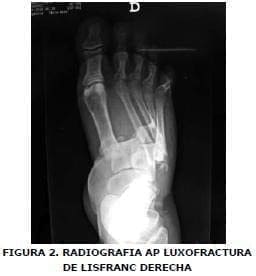

Se realizan radiografías y se hace diagnostico de fractura en articulación sacro ilíaca bilateral con subluxación del anillo pélvico superior de predominio izquierdo (Figura Nº 1), luxofractura de Lisfranc derecha (Figuras Nº 2 y 3), y luxofractura abierta tobillo izquierdo (Figura Nº4).

Se aplicó antibioticoterapia biconjugada y manejo de tejidos blandos. Quince días más tarde, se realizó reducción abierta con osteosíntesis definitiva con clavos de Kirschner en luxofractura de pie derecho tipo Lisfranc B2, con desplazamiento lateral. Encontrándose minutas en los metatarsianos (Figuras Nº 5 y Nº 6), en tobillo izquierdo se adelantó reducción abierta mas osteosíntesis con tornillos de esponjosa en superficie articular anterior de tibia distal y con clavo de Steinman se fijó articulación tibioastragalocalcanea, izquierda (Figura Nº 7). La paciente presento escaras sacras con evolución favorable y finalmente salió de alta hospitalaria a los 64 días de ocurrido el trauma.

Se aplicó antibioticoterapia biconjugada y manejo de tejidos blandos. Quince días más tarde, se realizó reducción abierta con osteosíntesis definitiva con clavos de Kirschner en luxofractura de pie derecho tipo Lisfranc B2, con desplazamiento lateral, encontrándose minutas en los metatarsianos (Figuras Nº 5 y Nº 6), en tobillo izquierdo se adelantó reducción abierta mas osteosíntesis con tornillos de esponjosa en superficie articular anterior de tibia distal y con clavo de Steinman se fijó articulación tibioastragalocalcanea, izquierda (Figura Nº 7).